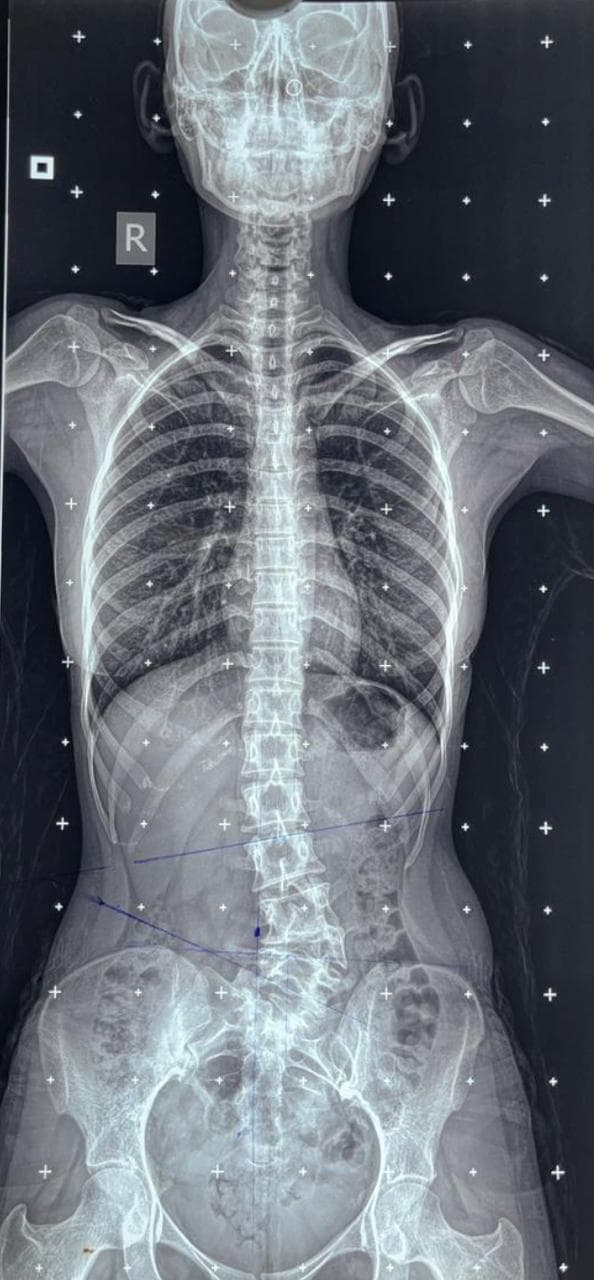

Scoliosis, an abnormal curvature of the spine, can significantly impact a person’s posture, balance, and quality of life, especially when present from birth. One such condition, congenital scoliosis, arises due to malformations in the spine during fetal development. A hemivertebra is a common cause of this, where a part of the vertebra fails to develop completely, leading to an asymmetric spinal curve that worsens over time.

This is the story of a 17-year-old girl who battled congenital scoliosis caused by a hemivertebra at the L4 level, and how timely surgical intervention helped transform her life.

A hemivertebra is a wedge-shaped vertebra that disrupts the normal alignment of the spine, often resulting in progressive scoliosis. When left untreated, especially in growing children and adolescents, the curvature tends to worsen with age, leading to severe spinal imbalance, chronic pain, restricted lung function, and psychosocial challenges.

In this patient’s case, the hemivertebra at L4 created a significant lumbosacral curve that affected the natural biomechanics of the spine, causing pain, a tilted posture, and aesthetic concerns.

The surgery was performed with high precision under intraoperative neuromonitoring to ensure spinal cord safety. Post-operatively, the patient:

Post-surgical rehabilitation included physiotherapy and core-strengthening exercises to enhance flexibility and prevent recurrence. Regular follow-ups ensured her spine healed well, and her quality of life improved substantially.